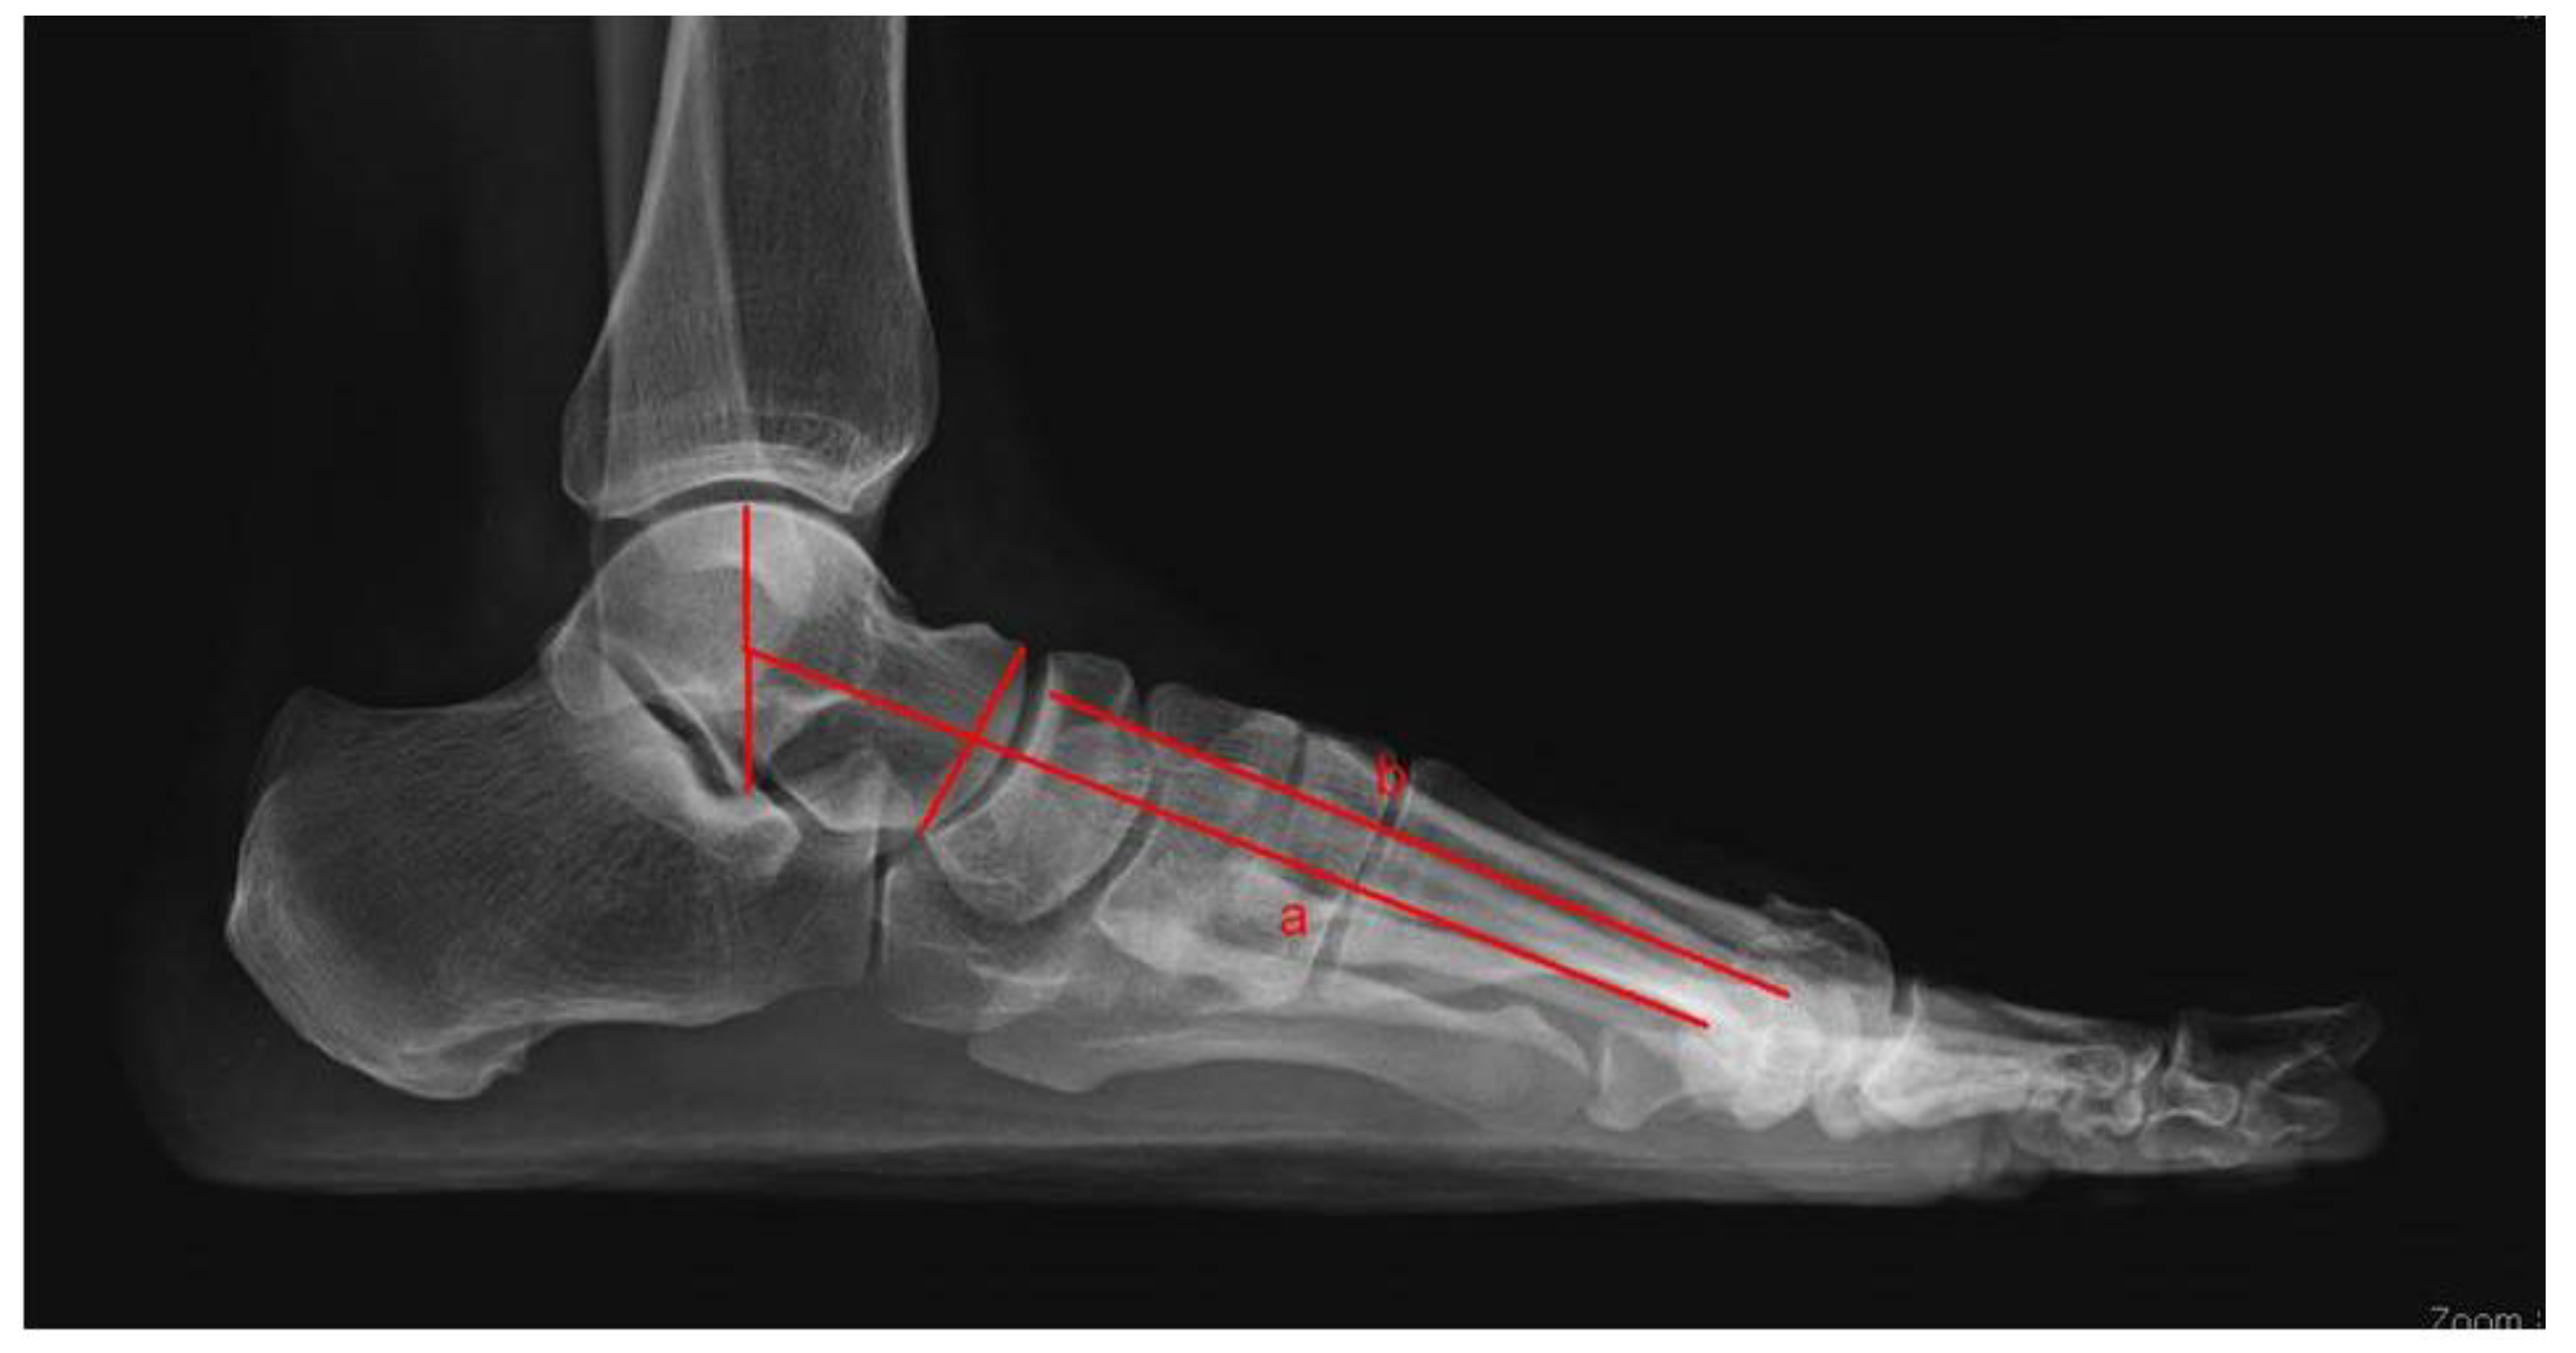

2. Materials and Methods